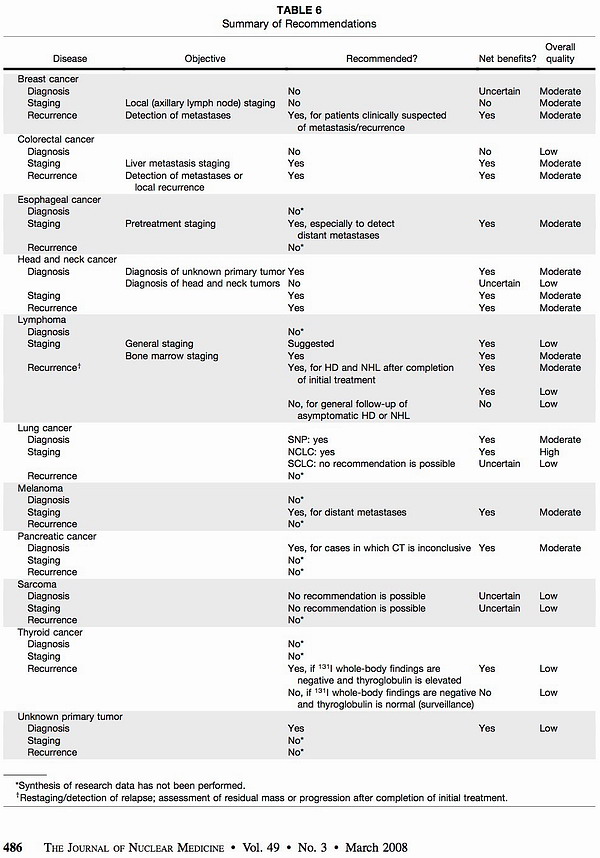

具体临床应用中,根据不同肿瘤的特性不同,可以参考下表[2],正确选择18F-FDG PET/CT检查的时间,充分发挥其增益价值。